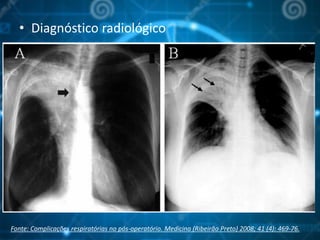

• Diagnóstico radiológico

Fonte: Complicações respiratórias no pós-operatório. Medicina (Ribeirão Preto) 2008; 41 (4): 469-76.

• Diagnóstico radiológico Fonte:Complicações respiratórias no pós-operatório. Medicina (Ribeirão Preto) 2008; 41 (4): 469-76.